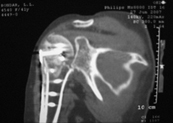

На консультативный прием обратилась женщина 42 лет, получившая 1.04.2007 бытовую травму:  закрытый оскольчатый перелом проксимального отдела левой плечевой кости со смещением отломков (b1_xr.jpg). 06.04.2007 оперирована в одном из отделений: открытая репозиция, накостный остеосинтез проксимального отдела левой плечевой кости. Выписана с заключительным диагнозом: а) основной: закрытый 4-х фрагментарный (по Ниру) перелом проксимального отдела левой плечевой кости, со смещением отломков; б) осложнения основного: нейропатия левого локтевого нерва;  в) сопутствующий: миокардитический миокардиосклероз ХСН 0-1.

В момент осмотра: нормостеническая конституция, по передней поверхности плечевого сустава – рубец. Рука в положении приведения. Отведение не более 10 град, дальнейшие движения с лопаткой до 20-25 град. Амплитуда сгибания-разгибания 10-15 град. Ротация отсутствует. Пальпаторно - выраженная болезненность над суставом, особенно в проекции клювовидного отростка. При попытках пассивных движений – боль. Рентгенограммы и результаты КТ приложены(b2(3)_xr.jpg, b1(6)_ct.jpg).

Диагноз: неправильно сросшийся в условиях накостного остеосинтеза оскольчатый перелом головки левой плечевой кости (11-С3.2), асептический некроз головки плечевой кости, смешанная артро-миогенная контрактура левого плечевого сустава; демиелинизирующая нейропатия левого локтевого нерва.

Анализ ситуации позволяет считать, что основными причинами контрактуры являются неправильная репозиция фрагментов головки (разворот кверху и кзади), асептический некроз головки плечевой кости (отчетливое склерозирование на СТ).